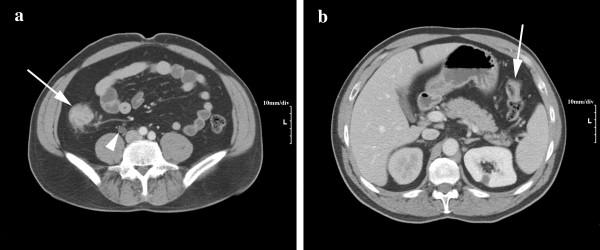

We report a 47 year-old male with hereditary nonpolyposis colorectal cancer (HNPCC) associated with a novel germline mutation in MLH1. This patient expressed a rare and severe phenotype characterized by three synchronous primary carcinomas: ascending and splenic flexure colon adenocarcinomas, and ureteral carcinoma. Ureteral neoplasms in HNPCC are most often associated with mutations in MSH2 and rarely with mutations in MLH1. The reported mutation is a two base pair insertion into exon 10 (c.866_867insCA), which results in a premature stop codon.

我们报告了一名 47 岁男性,患有遗传性非息肉病性结直肠癌 (HNPCC),与 MLH1 中的新种系突变相关。该患者表现出罕见且严重的表型,特征为三个同步原发性癌:升结肠和脾曲结肠癌,以及输尿管癌。HNPCC 中的输尿管肿瘤最常与 MSH2 突变相关,很少与 MLH1 突变相关。报道的突变是外显子 10 中的两个碱基插入 (c.866_867insCA),导致提前出现终止密码子。